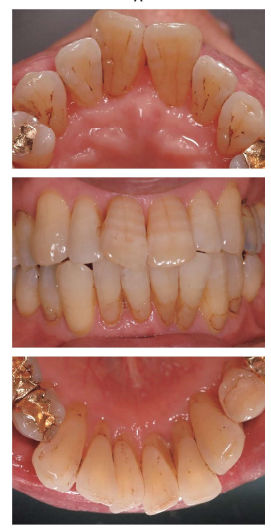

45歳の男性。下顎歯肉の腫脹と出血を主訴として来院した。検査の結果、慢性歯周炎と診断され、歯周治療を行うことになった。

初診時の正面観の口腔内写真(別冊午後No.10A)と下顎前歯部舌側両観の口腔内写真(別冊午後No.10B)を別に示す。

歯周基本治療開始前に説明すべきリスクはどれか。2 つ選べ。

解答:b d

解説:

Bの写真より歯頚部に歯石が見られる。歯石を取ると知覚過敏を引き起こしやすくなる。

また、歯間が広いため食片圧入は今もあると思われる。